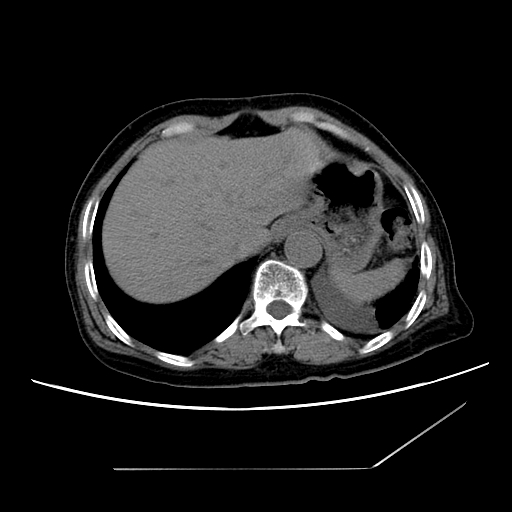

标题: CT25393:病人45岁,咳嗽,吐黄痰带血丝,发热,胸闷月余 [打印本页]

标题: CT25393:病人45岁,咳嗽,吐黄痰带血丝,发热,胸闷月余

1、左肺中央型肺癌并双肺弥漫性转移   2、双肺部感染    3、肺大泡     4、左侧胸腔积液

双侧肺弥漫性病变,可见“空泡征”及“蜂窝征”,考虑肺泡癌可能性大,左侧胸腔积液,考虑胸膜受累可能!

考虑肺泡癌,建议排除感染。

考虑肺泡癌

1)不排除肺泡癌可能。2)左侧胸腔积液。